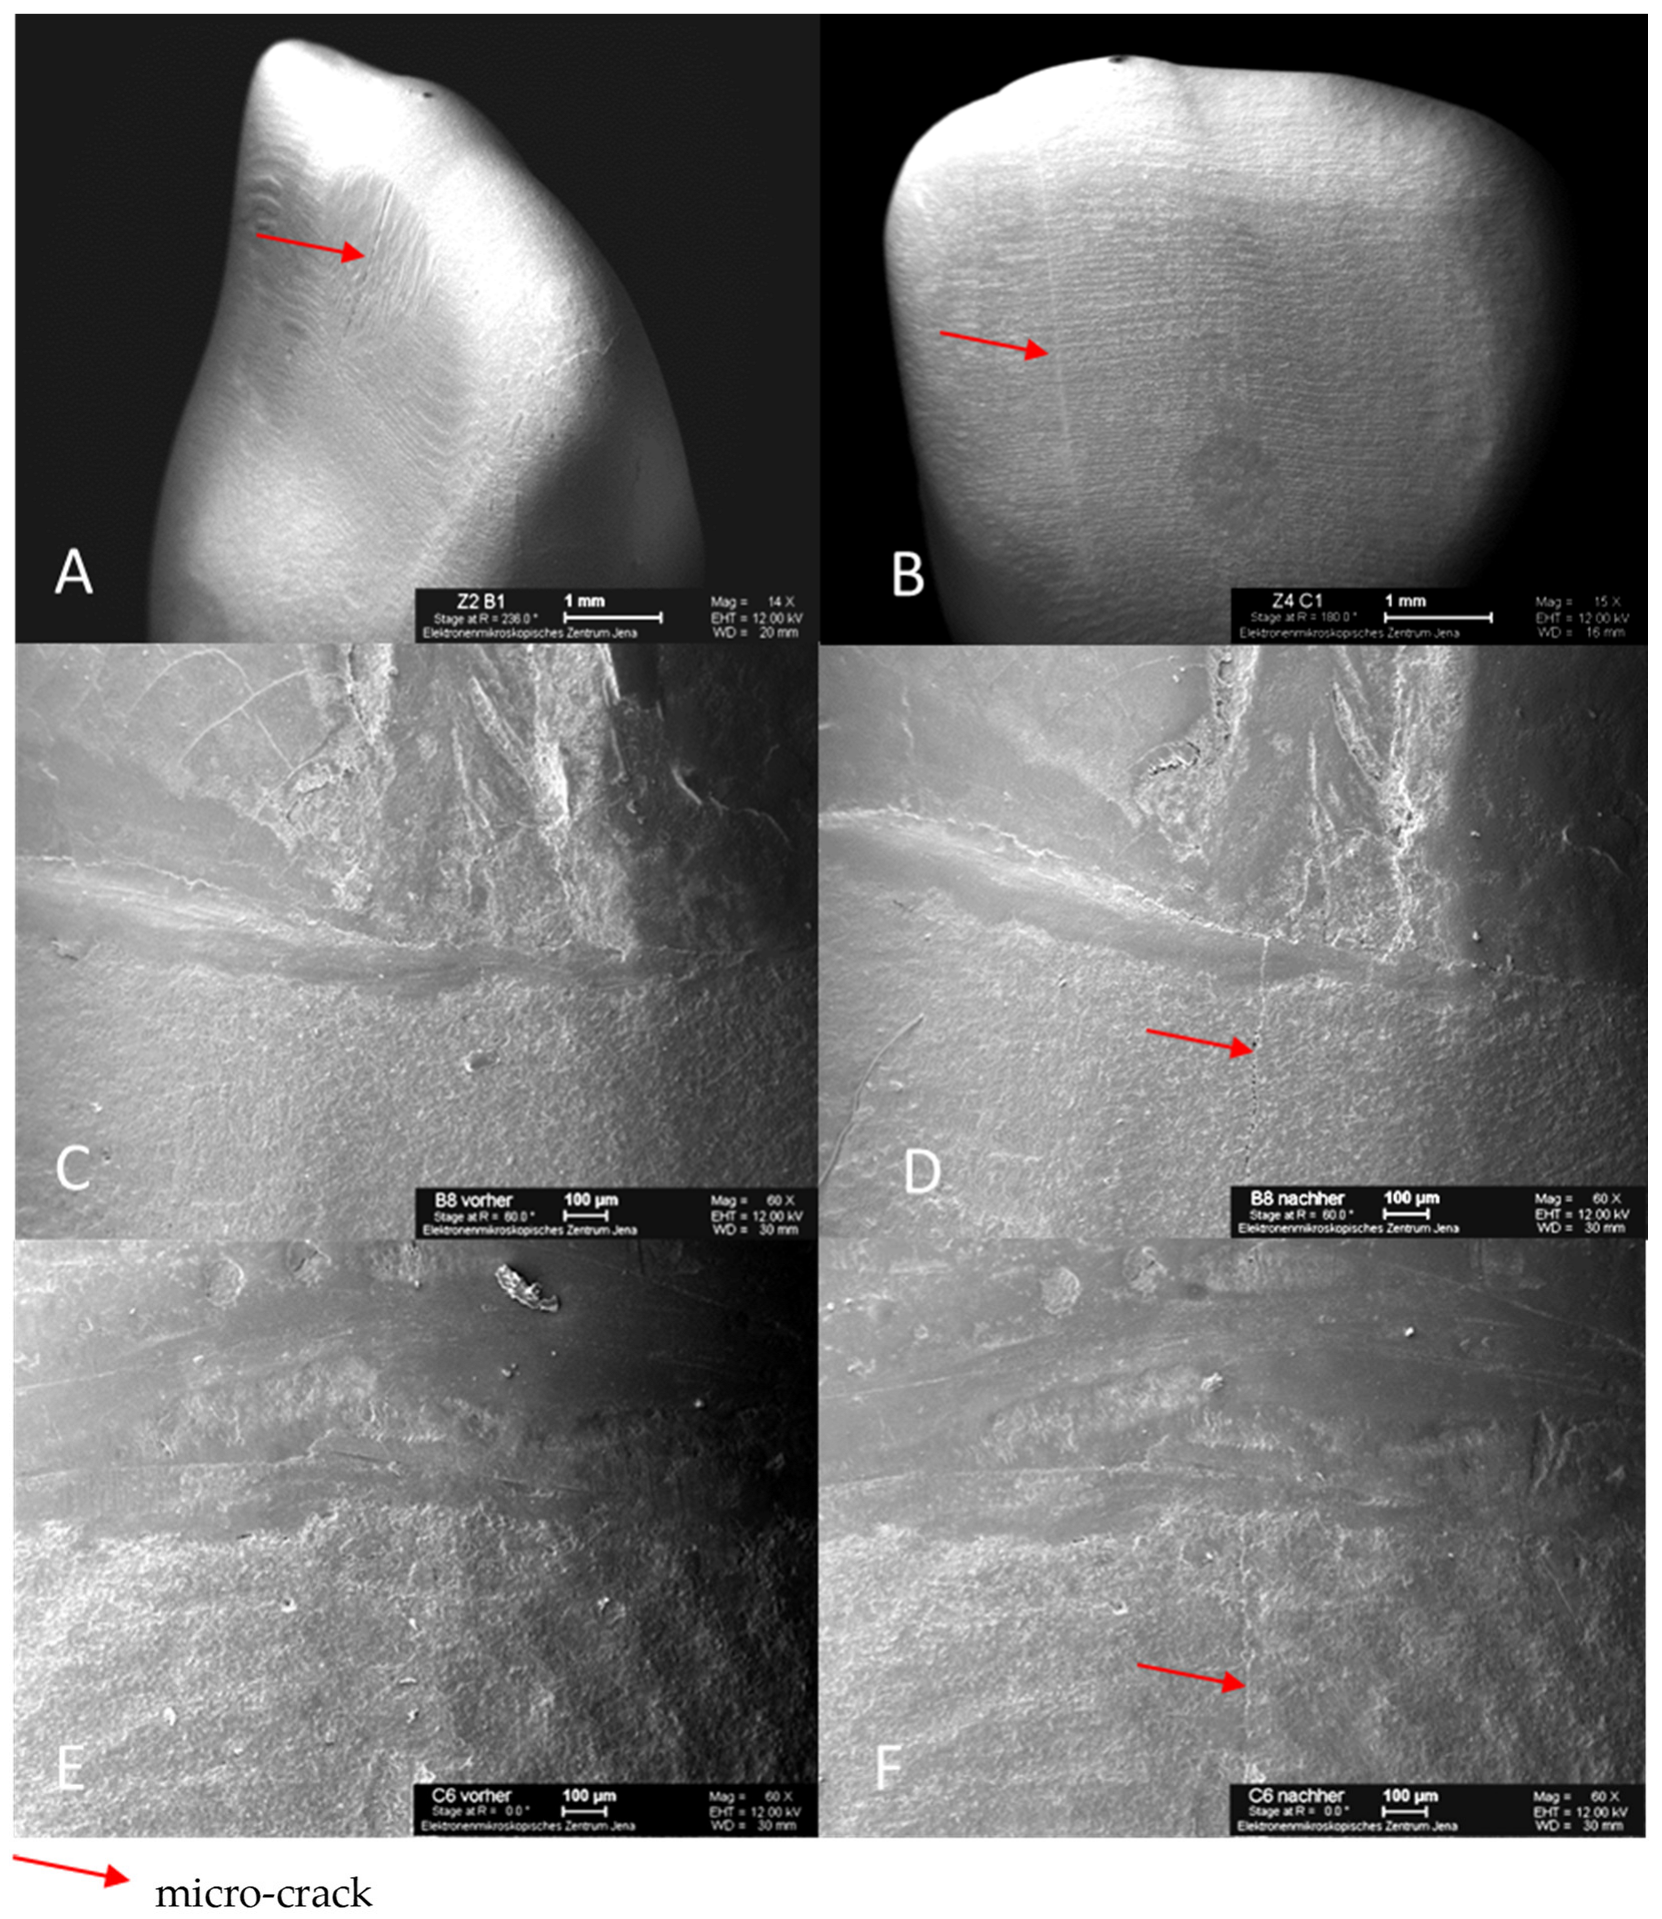

3.3. Analysis of Material Fatigue after Artificial Aging